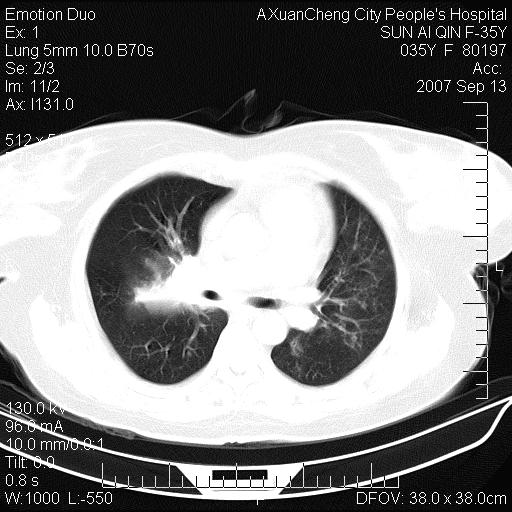

以下是引用天南地北在2007-9-13 13:43:00的发言:[br]考虑双肺、肺门侵润

以下是引用ydx_74在2007-9-13 15:42:00的发言:[br]仅看片,考虑右上肺癌并双肺转移,结合病史,考虑肺门、肺内淋巴侵润

以下是引用同在2007-9-13 15:08:00的发言:[br]支持肺门及双肺侵润.